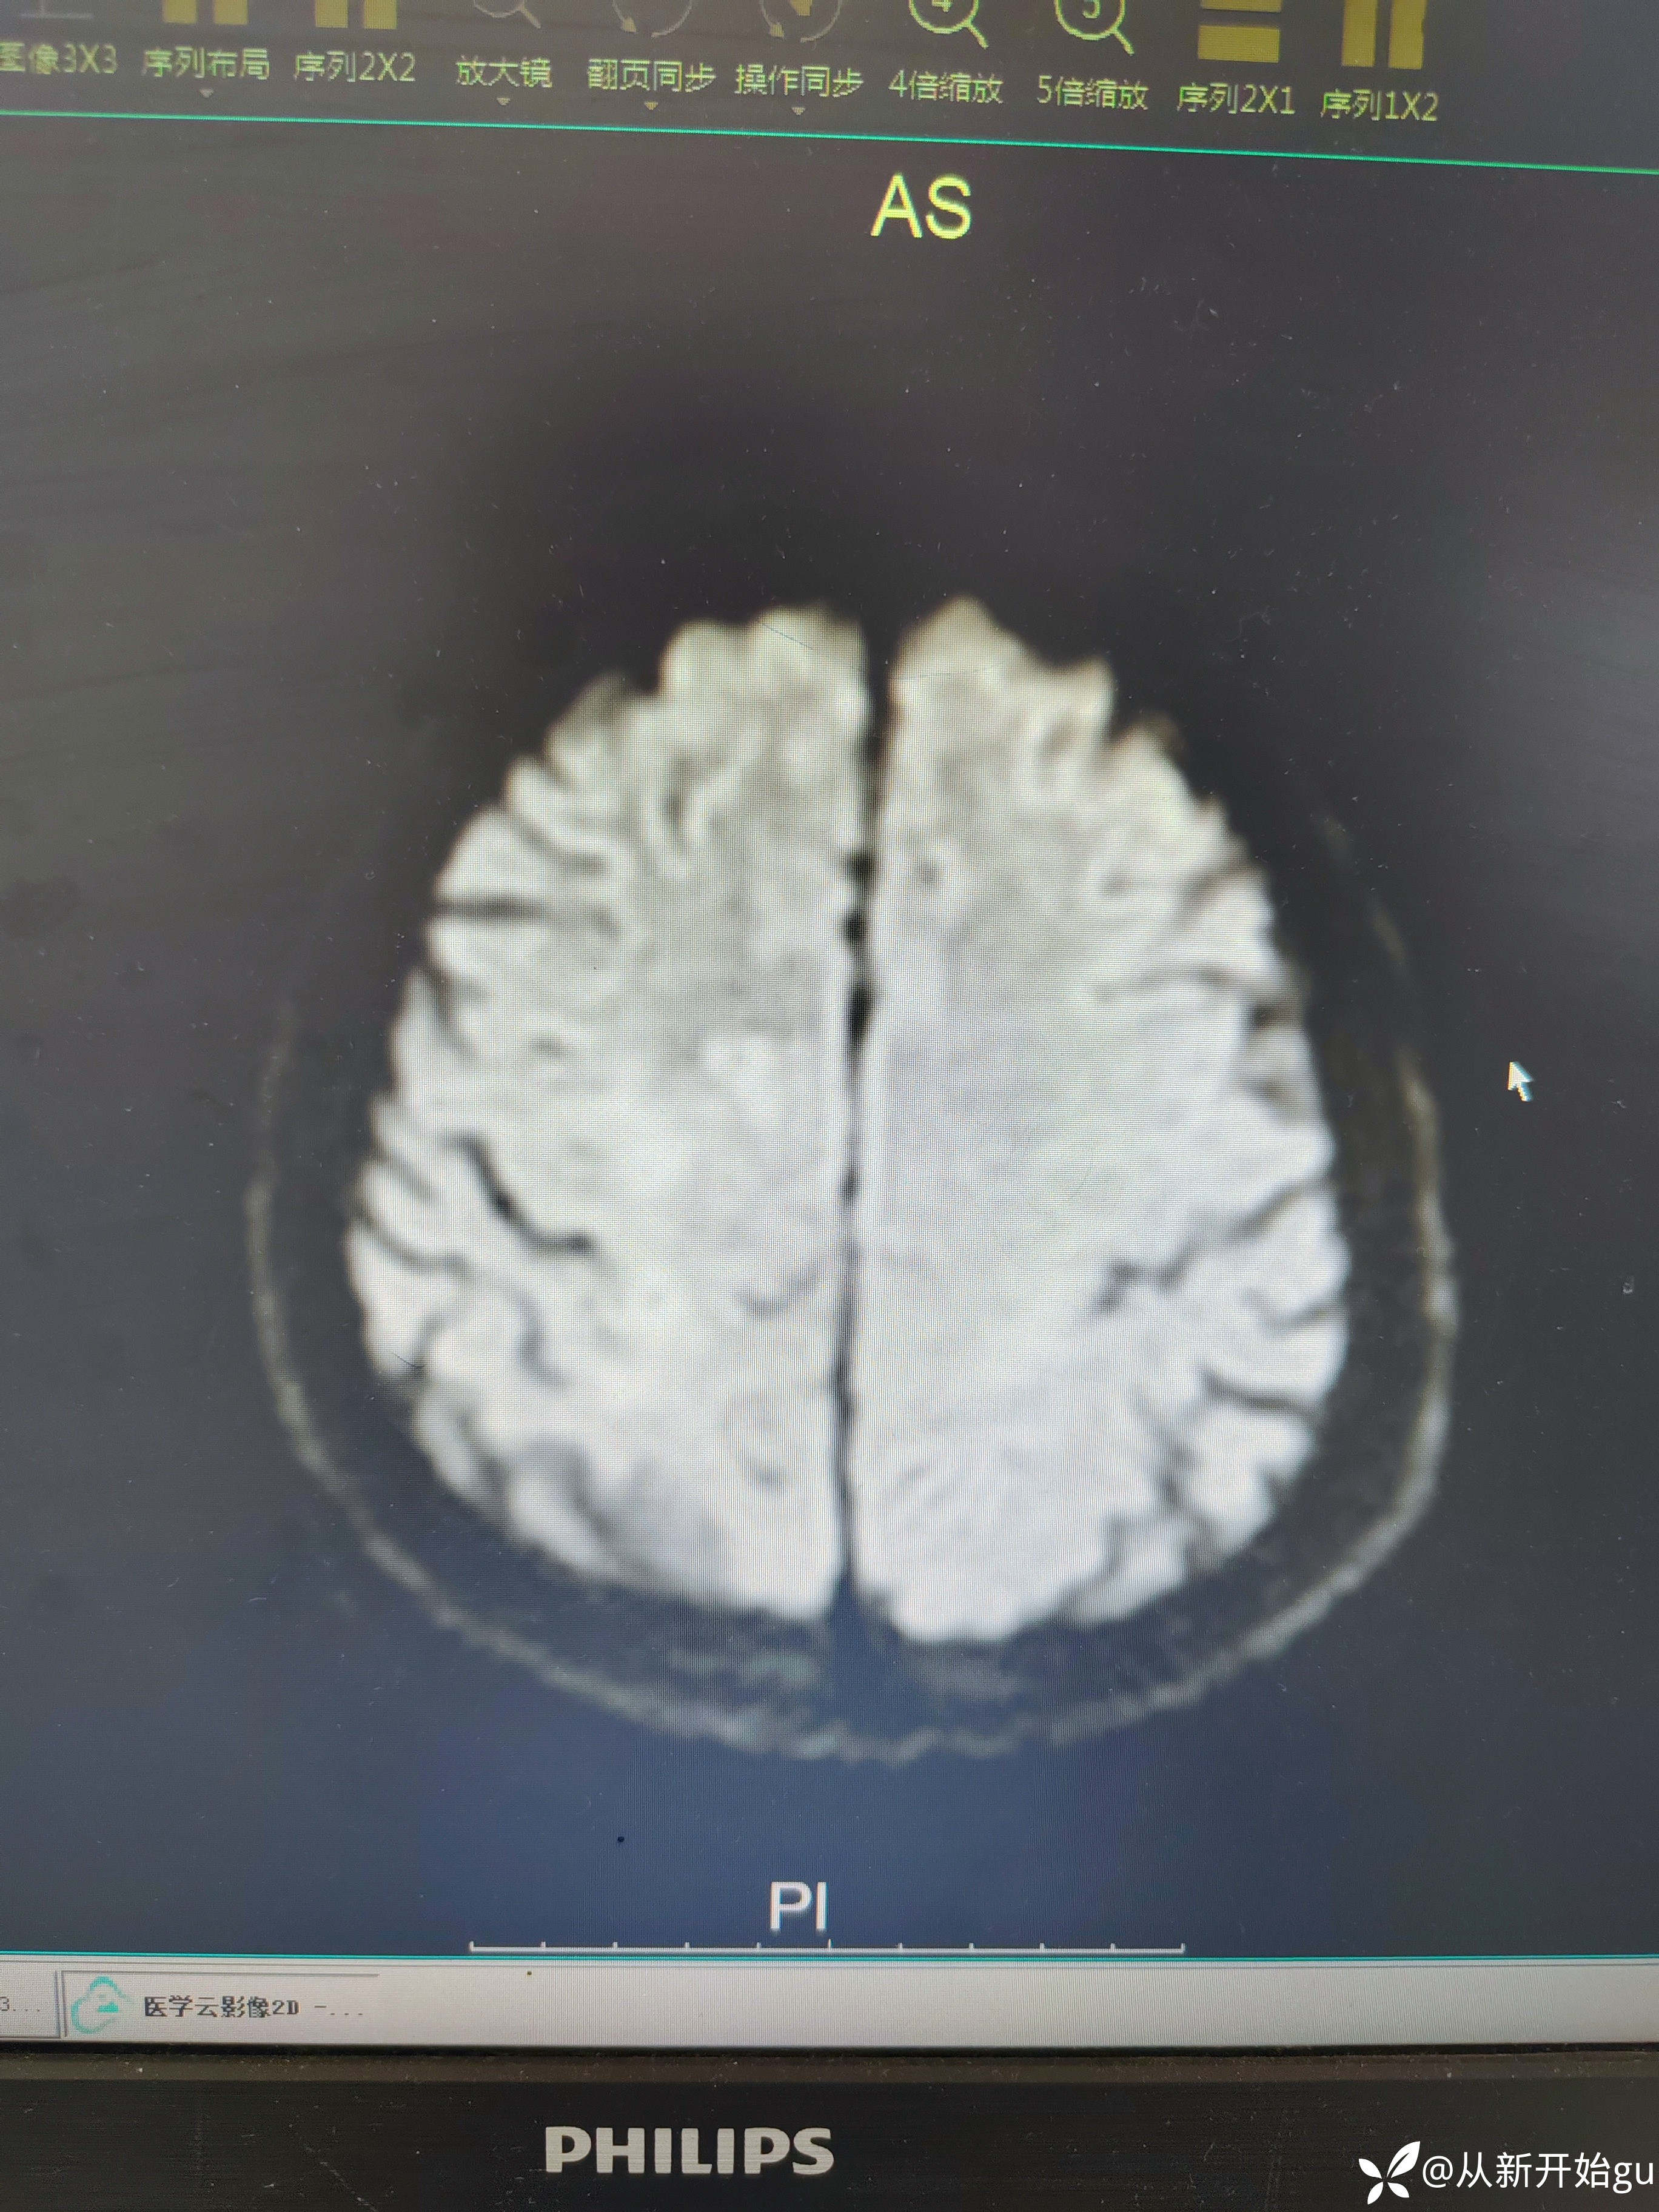

患者男性53岁,主因被发现左下肢活动障碍2.5小时来院,(患者下夜班,于上午9点休息,下午3点醒后出现症状)。既往脑梗死病史9个月,遗留言语不利及口角歪斜的症状。查体:右侧鼻唇沟稍浅,神舌右偏,左侧下肢肌力4级,左侧指鼻试验欠稳准,左侧巴氏征阳性。外院完善颅脑CT无出血改变。来院后完善核磁检查如图所示。